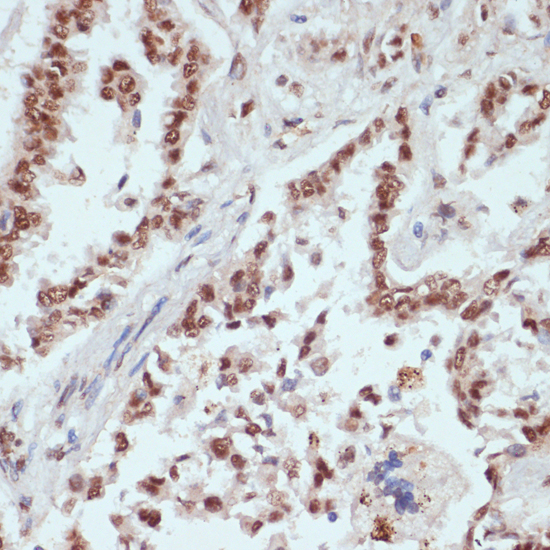

Immunohistochemistry of paraffin-embedded human colon carcinoma using Phospho-beta Catenin-S33/S37/T41 antibody. |